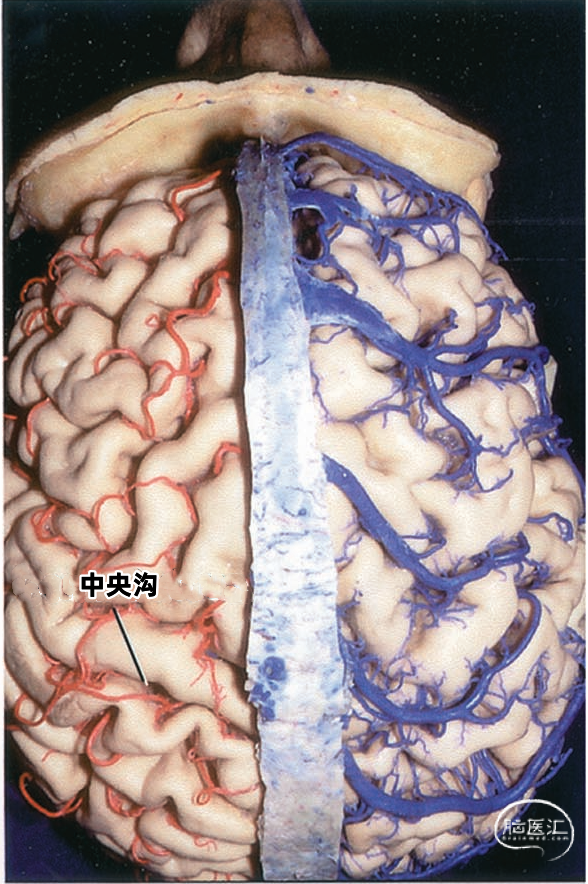

从两侧皮层汇入上矢状窦的皮层静脉具有特有的形态(下图)。左侧显示汇入上矢状窦的静脉,右侧显示静脉入窦的平均角度。从前到后,静脉入窦的角度逐渐减小。 额极附近的静脉,与上矢状窦内血流方向一致,汇入上矢状窦; 额叶后部的静脉向前汇入上矢状窦,与窦内血流的方向相反; 顶叶和枕叶的静脉向前汇入上矢状窦,与窦内血流方向相反;| 额极静脉 110° | 额前静脉 110° |

多数皮层静脉由单根起始,逐渐接受属支。相邻区域的皮层静脉可汇合成为一支桥静脉,穿出蛛网膜下腔,最后汇入硬膜窦。另外,引流半球内侧、外侧和底面的静脉,可能在交界区形成为一支桥静脉,最后汇入一个静脉窦。大脑内侧和外侧的上升静脉经常在半球上缘汇合,并进入上矢状窦;半球外侧下降的引流静脉和半球底面向外的引流静脉可在半球下缘汇合,进入颅底的硬膜窦。少数皮层静脉加入脑深部静脉系统。 相邻区域的血管间有互补关系,即某一静脉引流的区域增多,则相邻静脉的引流范围随之减少。在脑叶或面的主要引流静脉组之间也有类似的互补关系。

根据引流半球外侧面、内侧面或底面,皮层静脉分为三组。三个面的皮层静脉可依据其引流的脑叶和皮层区进一步细分。皮层静脉引流区域和方向如下: 额叶外侧面(蓝色)由额极静脉、额前静脉、额中静脉,额后静脉、中央前静脉、中央静脉、额外侧裂静脉引流。 顶叶外侧面(黄色)由中央静脉、中央后静脉、顶前静脉、顶后静脉、顶外侧裂静脉引流。 颞叶外侧面(绿色)由颞前静脉、颞中静脉、颞后静脉、颞外侧裂静脉引流。

▼1.额叶

额叶的引流静脉分为外侧面组、内侧面组、底面组。外侧面组分为上升组,汇入上矢状窦;下降组,引流向外侧裂,进入外侧裂浅静脉。 上升组静脉包括额极、额前、额中、额后静脉,中央前静脉和中央沟静脉。这些静脉可能在回流至上矢状窦前与相邻的底面组、内侧面组的静脉汇合; 下降组由额外侧裂静脉组成。上升组引流的区域大于下降组。 额叶外侧面静脉及其引流区域如下:额极静脉引流额下回、额中回和额上回前部;额前、额中、额后静脉引流额极和中央前回之间的额叶前、中、后部凸面;中央前静脉引流中央前回下部、额下回盖部和邻近的额下、额中和额上回;中央Rolandic静脉引流中央沟附近的中央前回和中央后回;额外侧裂静脉引流额下回和邻近的额中回下部及中央前回下部。 额叶内侧面由弯曲的扣带沟分为内侧区和外侧区。额内侧静脉分为上升组进入上矢状窦;下降组进入下矢状窦或汇入行经胼胝体的静脉,最后进入基底静脉前端。上升组静脉由前内侧额静脉、中内侧额静脉、后内侧额静脉和旁中央沟静脉组成,它们是额上回内侧和邻近扣带回的主要静脉回流,一般向上弯曲走行,在半球上缘向外加入来自半球外侧组的静脉,然后注入上矢状窦。下降组静脉包括胼周前静脉、终板旁静脉和大脑前静脉。 额叶内侧面静脉及其引流区域如下:额前内侧静脉引流额极后方的扣带回和额上回;额中间内侧静脉引流胼胝体膝部前方的额上回和邻近扣带回的内侧面;额后内侧静脉引流胼胝体膝部上方的额上回和扣带回;旁中央静脉引流胼胝体体部上方的扣带回和邻近的旁中央小叶;胼周前静脉为成对的静脉,引流胼胝体膝部和嘴部,以及邻近的扣带回;大脑前静脉引流胼胝体嘴部以下至视交叉上缘之间的区域;终板旁静脉引流胼胝体嘴部下方的终板旁回和嗅旁回区域。 额下静脉组,引流额叶眶面区域,可分为前组和后组:前组流向额极注入上矢状窦;后组引流向后,在外侧裂内侧集中于前穿质表面,形成基底静脉。前组由额眶前静脉和额极静脉组成;后组由嗅静脉和额眶后静脉组成。 额下静脉及其引流区域如下:额眶前静脉引流直回前部和眶回前内侧部;额眶后静脉引流额叶眶面后部;嗅静脉引流嗅沟及其邻近的直回和内侧眶回。

▼2.顶叶

顶叶的静脉根据引流分为顶叶外侧面组和顶叶内侧面组。 引流外侧面的静脉分为上升组和下降组。上升组汇入上矢状窦。下降组流入外侧裂静脉。上升组包括中央沟静脉和中央后静脉,还有顶前、后静脉。下降组由顶外侧裂静脉构成。 静脉及其引流区域如下:中央后静脉引流缘上回前部、顶上小叶和中央后回后部;顶前静脉引流缘上回和角回;顶后静脉引流顶下小叶后部和邻近的枕叶;顶外侧裂静脉引流中央后回和顶下小叶。 顶内侧静脉分为向上汇入上矢状窦的上升组和向下绕过胼胝体压部进入Galen静脉或其属支的下降组。上升组包括旁中央沟静脉、顶前内侧静脉和顶后内侧静脉。下降组为胼周后静脉。顶叶内侧面和外侧面的上升静脉经常在汇入上矢状窦前先在半球上缘汇合。旁中央沟静脉引流相邻的额叶和顶叶,与额内侧静脉一起描述。 顶内侧静脉及其引流区域如下:顶前内侧静脉引流扣带回上缘和楔前叶前部;顶后内侧静脉引流楔前叶后部和邻近的枕叶;胼周后静脉成对,引流胼胝体、扣带回和楔前叶后部。

上矢状窦组(上图 深蓝色)由回流至上矢状窦的静脉组成,包括引流额叶、顶叶、枕叶内侧、外侧面上部皮层以及额叶眶面前部的静脉。 注入上矢状窦的大脑外侧面静脉包括额极静脉、额前静脉,额中静脉、额后静脉,中央前静脉、中央静脉、顶前静脉、顶后静脉、枕静脉和Trolard静脉。 注入上矢状窦的大脑内侧面静脉(上图 蓝色)包括额前内侧静脉,额中内侧静脉、额后内侧静脉、旁中央沟静脉、顶前内侧静脉、顶后内侧静脉和距状后静脉。 一般静脉在离开软膜-蛛网膜注入上矢状窦前,会在硬膜下腔有1~2cm长的游离段。这些静脉可能直接汇入上矢状窦,也可能先汇入硬膜内的硬膜窦,再进入上矢状窦。

沿大脑镰至胼胝体前部的手术入路往往需要牺牲一支进入上矢状窦的桥静脉。偶尔也可以在额前、后静脉之间达到胼胝体,而不用损伤桥静脉。这是因为经常在额前和额中静脉、或额中和额后静脉之间,有几厘米长的上矢状窦没有静脉注入(下图)。 在中央前回、中央沟或中央后回处损伤进入上矢状窦的桥静脉(下图)经常会导致对侧肢体的偏瘫,而且下肢比上肢症状明显,一般是暂时性的。这些部位的自发性静脉梗塞除导致偏瘫外,一般伴有头痛和癫痫。